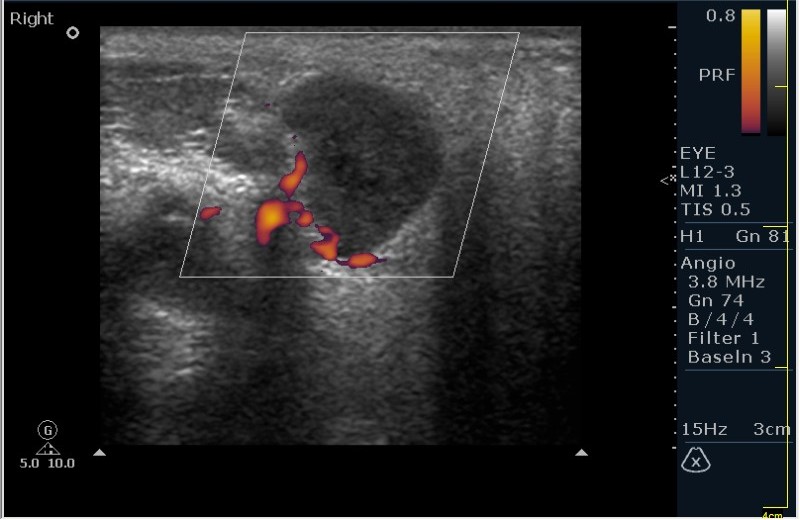

Доктор Марио! Судя по сонограммам это слюнная железа. Но почему за ухом? Околоушная железа лоцируется впереди уха, в области височно-нижнечелюстного сустава. Образование овальной формы, гипоэхогеное, с четкими ровными, контурами. Структура неоднородная с гиперэхогенными ячеистыми включениями. Рядом расположены еще два подобных образования, гораздо меньших размеров. Сосуды образованием оттеснены. Клиника скудная, а то бы подумал на аденофлегмону. Однажды встречал подобное. Оказалась аденома из рудиментов жабер. В общем необходимо выполнить ТАБ. Станет все ясно. В.Е.